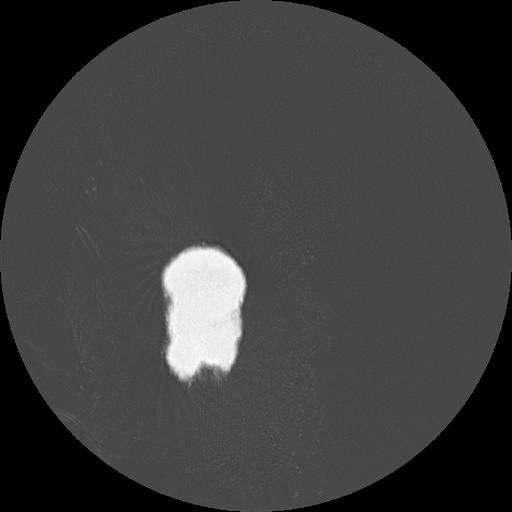

7 HUESO,,Vol,0.5,HUESO,,